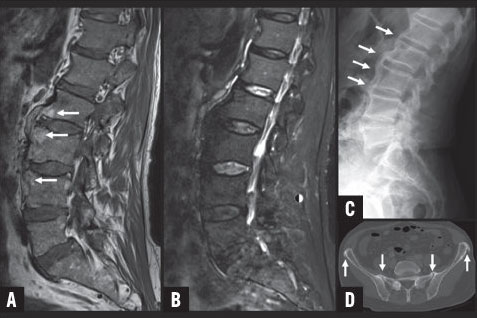

Quelle est la différence entre un scanner et un irm. Radiologie paris ouest rpo groupe de centres de radiologie générale et spécialisée à paris vous propose de vous éclairer sur la différence entre ces deux notions. Lexamen par irm nexpose donc pas le patient aux rayons x. Lexamen se fait dans une machine avec un aimant et peut durer entre 30 minutes et une heure. Très souvent les patients confondent le scanner et lirm alors que ce sont deux techniques très différentes. Lirm utilise en effet un champ magnétique qui crée un signal différent selon les parties du corps observées. Lirm en revanche est un processus plus long du fait de limportance et de la complexité du placement du patient dans le tunnel. Ils ont également des différences fondamentales à lorigine dindications spécifiques selon lâge du patient la région anatomique explorée ou la pathologie recherchée. La plus grande différence réside en ce que lirm fait appel à un gros aimant et à des ondes radio pour générer les images tandis que la tomodensitométrie fait appel aux rayons x. La radiographie est née à la fin du xix e siècle avec lutilisation des rayons x. Scanner et irm ont un certain nombre de points communs importants. Un scanner médical est un appareil dimagerie à rayons x qui permet létude de structures anatomiques en employant la technique par coupes puis par traitement informatique à numériser afin de réaliser des images 2d ou 3d. Aussi certains appareils sont ils dotés dun écran projetant des dessins animés pour les enfants. Différence entre scanner et irm. En effet le scanner utilise les rayons x et se base sur labsorption des rayons par les tissus de lorganisme. Quest ce quun scanner. Même si dans les deux cas le patient est placé dans un tube pour son examen médical la première différence entre le scanner et lirm vient du principe sur lequel la technique repose. Quelle est la différence entre un scanner et une irm. Le scanner utilise les rayons x. Puis de nouvelles techniques dimagerie médicale sont apparues telles que le scanner et lirm imagerie à. Lirm a lavantage de donner des images dans les trois plans de lespace et détudier la colonne vertébrale lombaire dans son ensemble.

Quelle est la différence entre un scanner et un irm. Radiologie paris ouest rpo groupe de centres de radiologie générale et spécialisée à paris vous propose de vous éclairer sur la différence entre ces deux notions. Lexamen par irm nexpose donc pas le patient aux rayons x. Lexamen se fait dans une machine avec un aimant et peut durer entre 30 minutes et une heure. Très souvent les patients confondent le scanner et lirm alors que ce sont deux techniques très différentes. Lirm utilise en effet un champ magnétique qui crée un signal différent selon les parties du corps observées. Lirm en revanche est un processus plus long du fait de limportance et de la complexité du placement du patient dans le tunnel. Ils ont également des différences fondamentales à lorigine dindications spécifiques selon lâge du patient la région anatomique explorée ou la pathologie recherchée. La plus grande différence réside en ce que lirm fait appel à un gros aimant et à des ondes radio pour générer les images tandis que la tomodensitométrie fait appel aux rayons x. La radiographie est née à la fin du xix e siècle avec lutilisation des rayons x. Scanner et irm ont un certain nombre de points communs importants. Un scanner médical est un appareil dimagerie à rayons x qui permet létude de structures anatomiques en employant la technique par coupes puis par traitement informatique à numériser afin de réaliser des images 2d ou 3d. Aussi certains appareils sont ils dotés dun écran projetant des dessins animés pour les enfants. Différence entre scanner et irm. En effet le scanner utilise les rayons x et se base sur labsorption des rayons par les tissus de lorganisme. Quest ce quun scanner. Même si dans les deux cas le patient est placé dans un tube pour son examen médical la première différence entre le scanner et lirm vient du principe sur lequel la technique repose. Quelle est la différence entre un scanner et une irm. Le scanner utilise les rayons x. Puis de nouvelles techniques dimagerie médicale sont apparues telles que le scanner et lirm imagerie à. Lirm a lavantage de donner des images dans les trois plans de lespace et détudier la colonne vertébrale lombaire dans son ensemble. La discussion suivante de la quelle est la différence entre un scanner et un irm que collecter. L'administrateur Diverses Différences 2019 collecte également d'autres images liées quelle est la différence entre un scanner et un irm en dessous de cela. Visitez l'adresse source pour une explication plus complète.